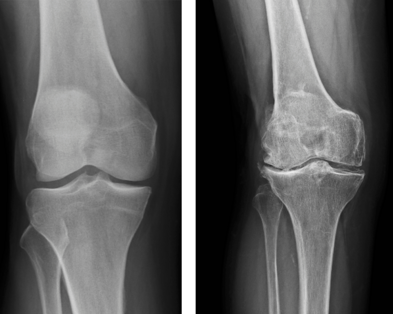

Diagnosi

La diagnosi di artrosi si basa su visita specialistica ortopedica, valutazione clinica, radiografie e talvolta risonanza magnetica.

Il trattamento dipende dallo stadio della malattia: esercizi mirati, fisioterapia, infiltrazioni ecoguidate con acido ialuronico o PRP, fino alla sostituzione protesica nei casi più gravi.